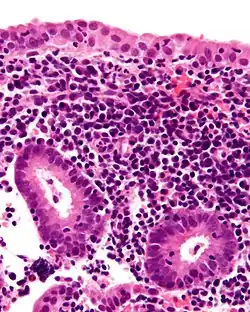

Coupe histologique présentant une endométrite chronique, avec des plasmocytes, caractéristiques ; des granulocytes neutrophiles sont également présents de manière éparse. Coloration à l'hématoxyline et à l'éosine.